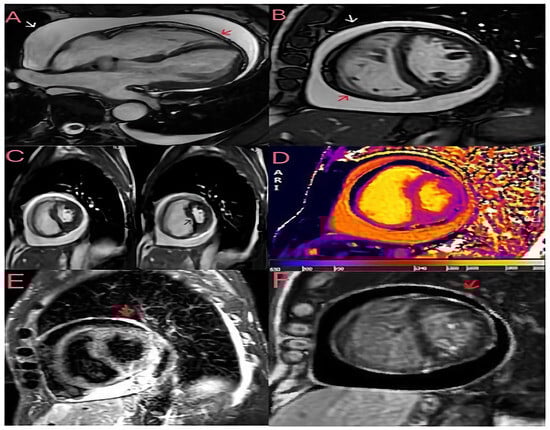

Figure 2. Cardiac magnetic resonance imaging (CMRI) was performed to assess the patient’s pericardial disease prior to referral to cardiac surgery. Breath-hold steady-state free precession (SSFP) cine of bright blood horizontal long axis (A) and midventricular short axis (B) views with evidence of a large pericardial effusion without compression of the ventricles in late diastole. The visceral (red arrow) and parietal (white arrow) pericardial layers are slightly thickened (3 mm). (C) Free-breathing SSFP cine in real time showing ventricular interdependence as a sign of constrictive pathophysiology; the left panel was taken during expiration, and the right panel during inspiration, showing septal bounce (black arrow) and crushing of the left ventricular chamber during inspiration. (D) The native T1 mapping sequence (modified look-locker inversion recovery) shows increased T1 times in the pericardium. (E) A short tau inversion recovery (STIR) T2 sequence showing pericardial hyperintensity (red arrow) compatible with oedema. (F) A late gadolinium enhancement (LGE) phase-sensitive inversion recovery (PSIR) sequence showing increased signal intensity in the pericardial layers (red arrow). The finding of a large pericardial effusion without tamponade and the widespread inflammation on the tissue characterisation images suggest subacute pericarditis with transient constrictive physiology, which accounts for 9–17% of cases of constrictive pericarditis and may resolve spontaneously within a few months [2,3]. Consequently, the patient was started on anti-inflammatory treatment with 600 mg of ibuprofen three times daily and 1 g of colchicine daily, resulting in clinical improvement, normalisation of inflammatory markers and discharge to home. During the follow-up, ibuprofen was progressively tapered to discontinuation, and at the last follow-up visit in October 2024, the patient was asymptomatic with no signs of volume overload and a normal plasma protein C level. This clinical case highlights the importance of assessing the chronicity of the disease by imaging in patients with constrictive pericarditis to differentiate between chronic and transient constriction, as acute/subacute cases may respond to medical therapy. Even though TTE is the imaging modality of choice for haemodynamic assessment, tissue characterisation with CMR is essential to diagnose the different phases of the pericardial inflammatory process, helping to differentiate an acute/subacute process (STIR+ and LGE+) from a chronic one (LGE+ and STIR-). Also of fundamental importance is the ability of cardiac magnetic resonance imaging to better assess the extent of pericardial effusion and pericardial thickening (a thickness > 3 mm tends to indicate chronic constrictive pericarditis). Such differentiation is crucial for tailored therapy; indeed, pericardiectomy is required in appropriate patients with chronic constrictive pericarditis [4]. In contrast, anti-inflammatory therapy is preferred in patients with transient constrictive pericarditis [5].